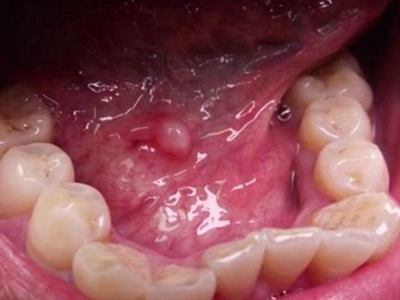

口腔尖锐湿疣是由人乳头瘤病毒感染引起的发生于口腔黏膜的性传播疾病,主要由HPV6、11等型引起。引起尖锐湿疣的某些HPV亚型与癌的发生有关,表现为疣状结节。口腔尖锐湿疣多由口交感染引起,好发生于性活跃的青、中年。

口腔尖锐湿疣好发于舌、牙龈、腭等部位,表现为单个或多个无痛性的疣状结节,有蒂或无蒂,可逐渐增大或融合,形成菜花状、乳头状赘生物,颜色呈肉色或苍白色,患者可有异物感。